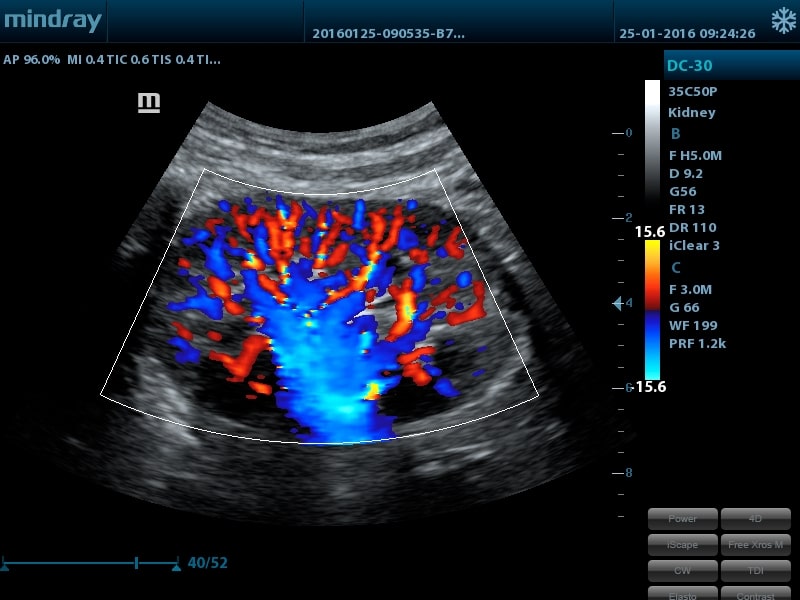

Многофункциональные УЗИ сканеры Mindray DC-28, DC-30 и DC-32 зарегистрированы в РФ 13 февраля 2018 г. УЗИ сканеры этой серии можно отнести к ультразвуковым аппаратам начального/среднего уровня, которые имеют не только конкурентоспособные цены, но и отличаются рабочими характеристиками, которые позволяют получать высококачественные изображения.

- Режимы сканирования: B, M, цветовой доплер CDI, цветной M-режим, энергетический и направленный энергетический доплер PD, Dir-PD, PW (включая HPRF)

- UWN Contrast Imaging™ - опция нелинейной визуализации в ультрашироком диапазоне для проведения обследования с применением контрастных веществ (поддерживается на датчике 35С50Р)

- Конвексный датчик 35C50P, 1,8 - 6,0 МГц, R50мм, 80 элементов